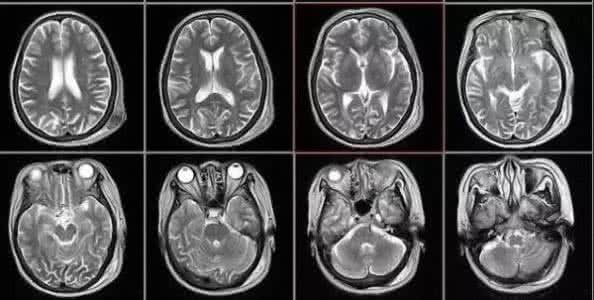

核磁共振:摇一摇再看

核磁共振机使用较强大的磁场,使人体中所有水分子磁场的磁力线方向一致,这时磁共振机的磁场突然消失,身体中水分子的磁力线方向,突然恢复到原来随意排列的状态。简单说就相当于用手摇一摇,让水分子振动起来,再平静下来,感受一下里面的振动。所以,核磁共振(MRI)也被戏说为是摇摇看的检查。

颈椎病、腰椎间盘突出等椎间盘疾病需要观察椎间盘与相应的神经根,要想更好观察这些软组织,最优选择就是核磁。同样,对于关节、肌肉、脂肪组织检查,核磁也是首选。